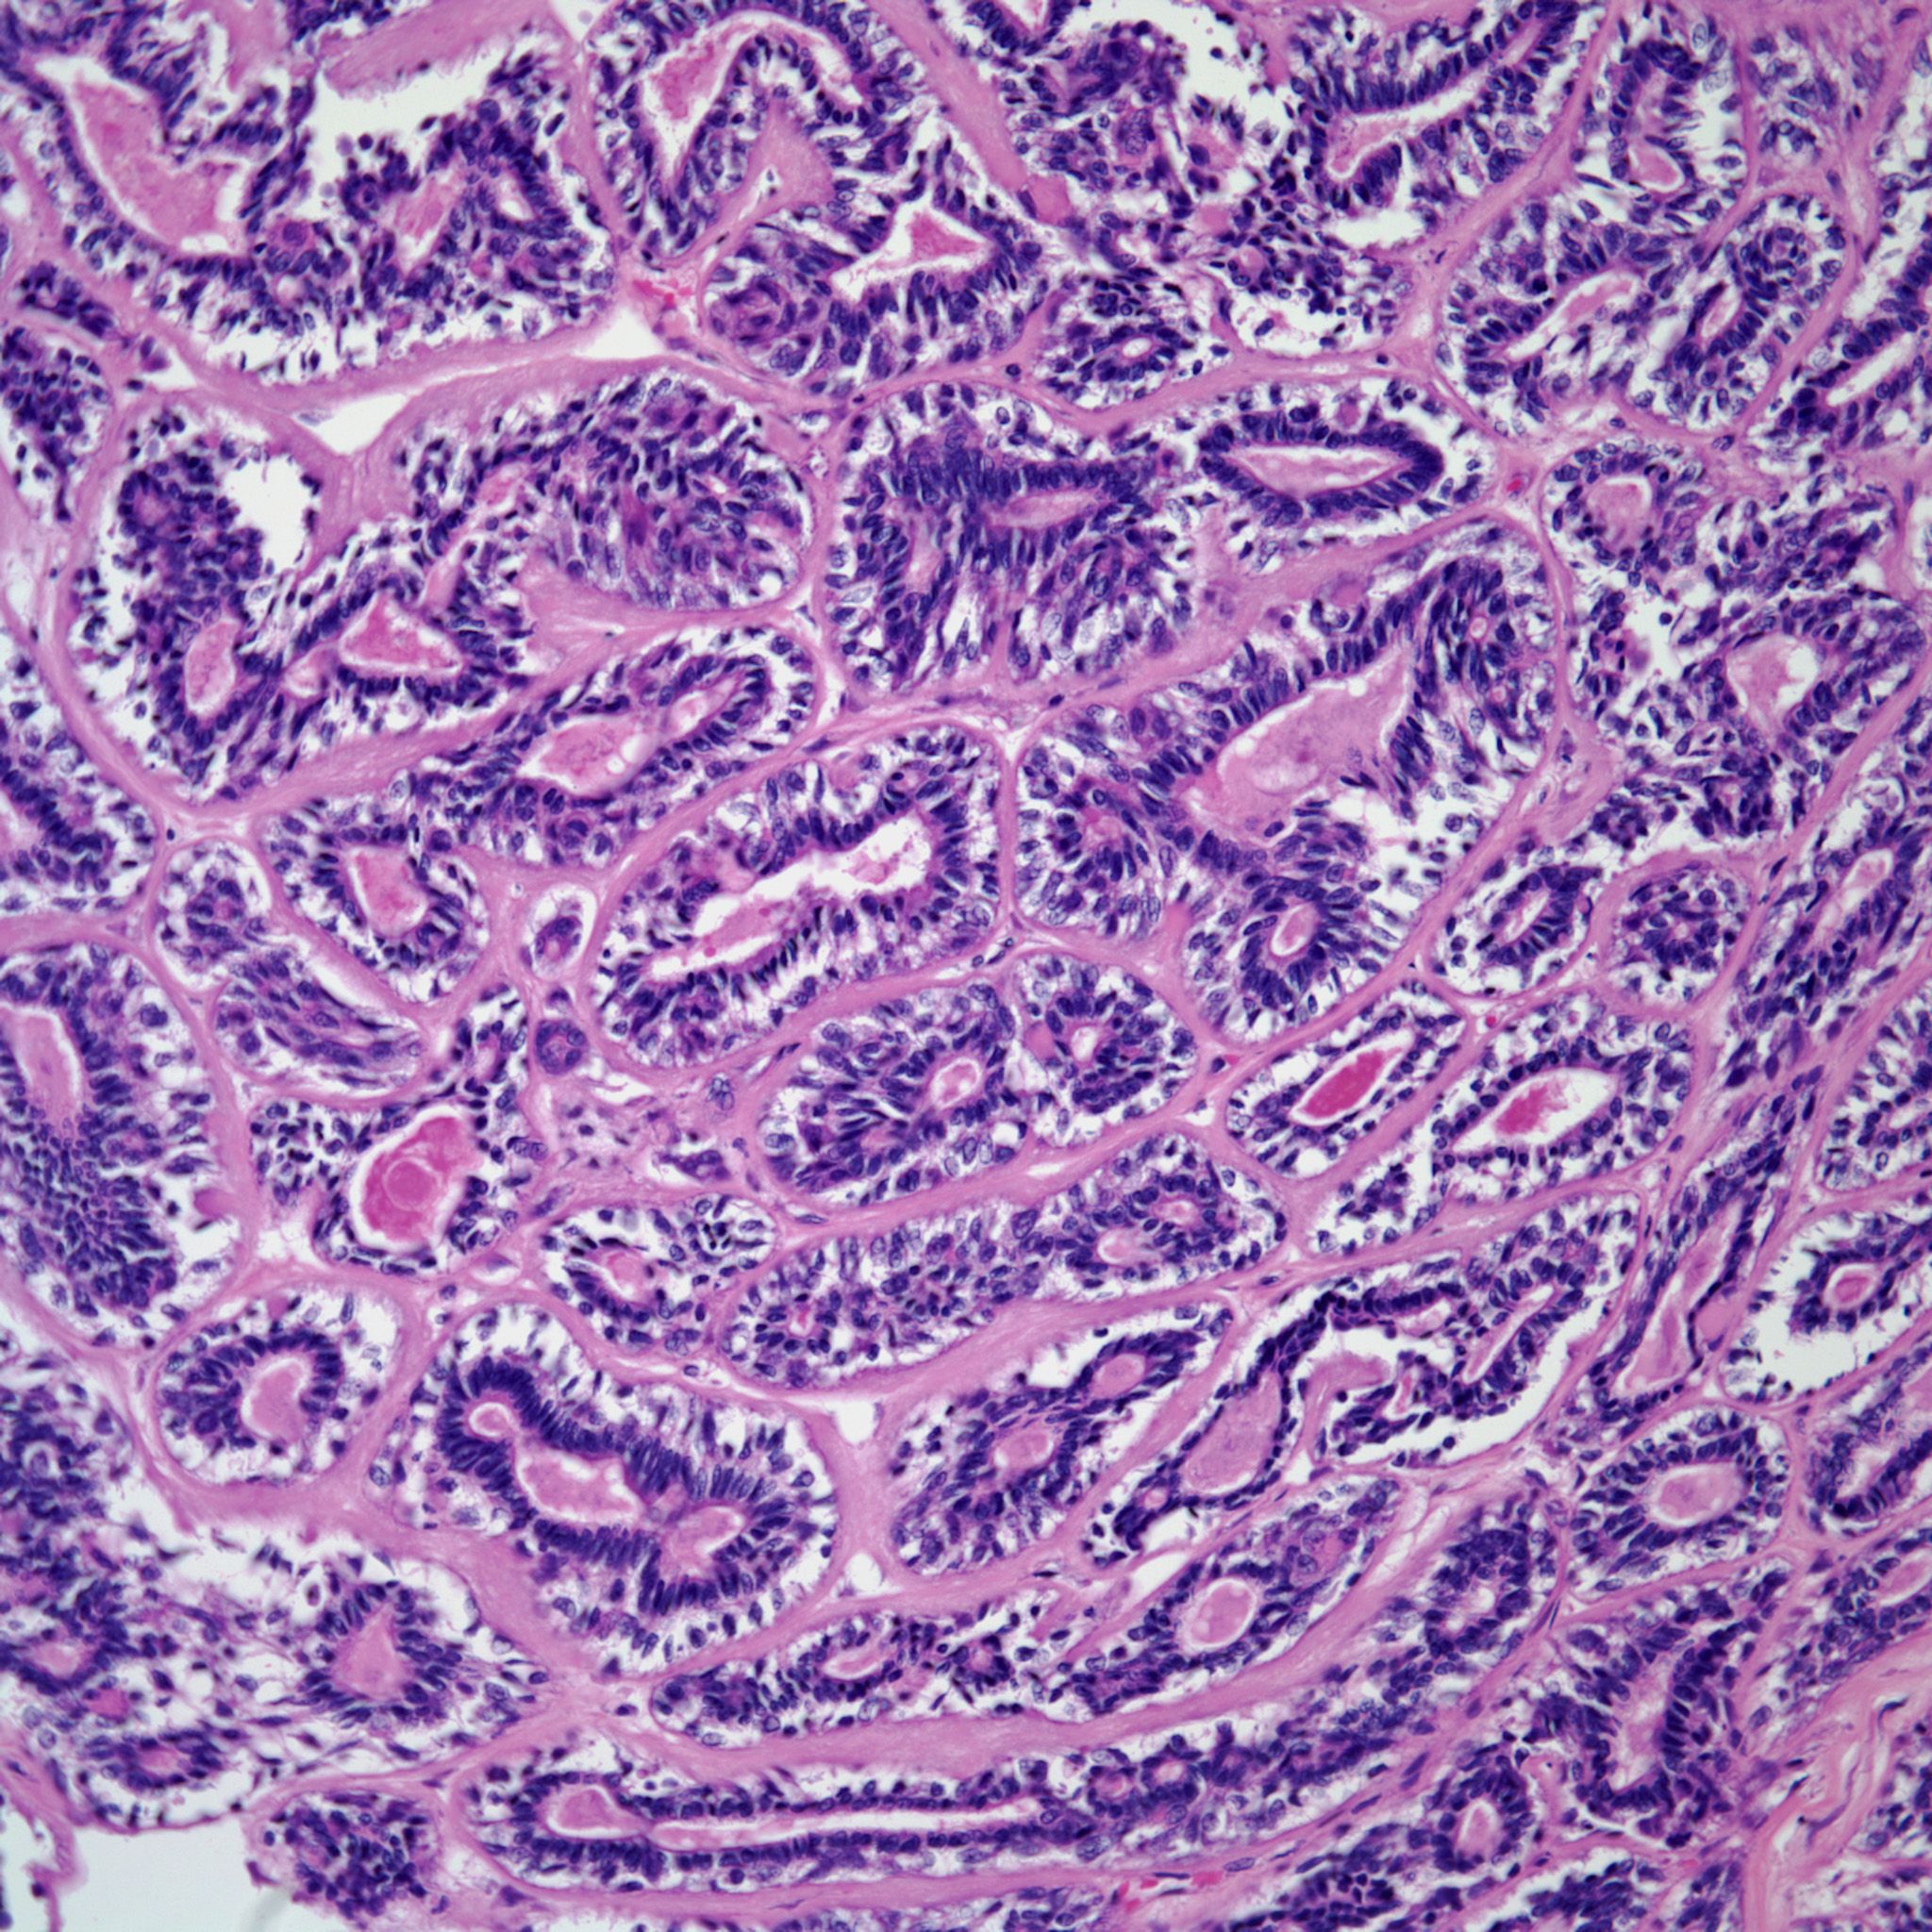

A 43-year-old woman presents with symptoms of dyspnea, wheezing, and shortness of breath. Diagnostic imaging reveals a tumor mass partially obstructing the bronchus of the left lung. The patient does not have any other pertinent history and states that she has been well until now. Surgical resection of the left lower lobe is performed. Grossly, the tumor measures approximately 2.5 cm in greatest dimension, is described as light tan to brown, well-circumscribed, but not encapsulate. Areas of necrosis and/or hemorrhage were not present.

Based on the image shown, what is your diagnosis?